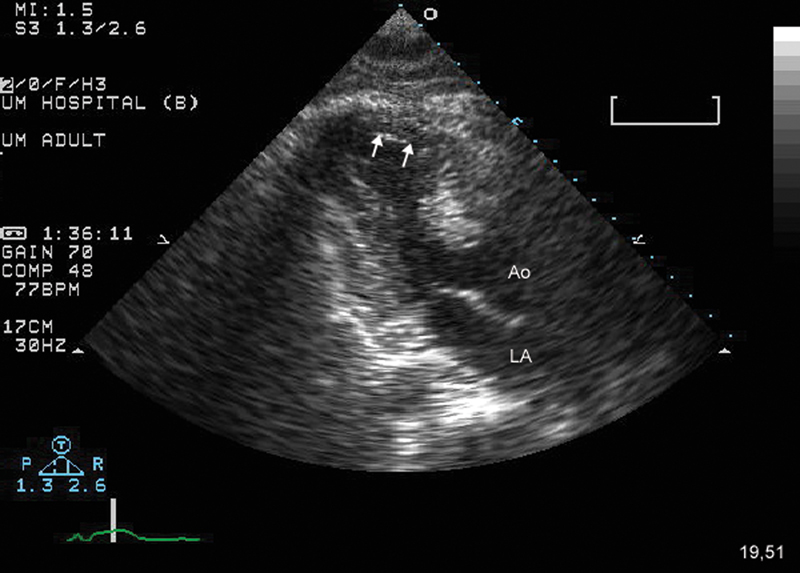

فحوصات تشخيصية لبعض امراض القلب والشرايين التاجية